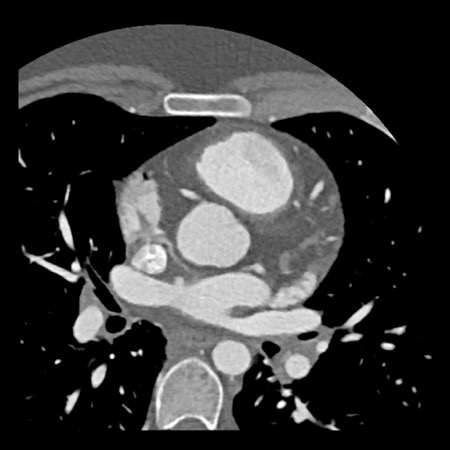

case 4 – CAD-RADS 3/P1/I+ thrombus left ventricle

The findings are:

- Moderate (50-69%)

stenosis in the proximal LAD caused by a non-calcified plaque. - Variant of

sinoatrial (SA) nodal artery. The artery usually arises from the RCA as a second

branch after the conus artery, however in this case it arises from the LCX,

courses behind the aorta, anastomosing with the right atrium and with a small

branch supplies the SA-node of the heart. - Thrombus in the

apex of the left ventricle. - CTP was performed

in this patient. CTP showed a perfusion defect at stress imaging in the

territory of the LAD (I+), at rest no perfusion defect was visible.

This patient classifies as CAD-RADS 3/P1/I+, which means

this patient requires further investigation.